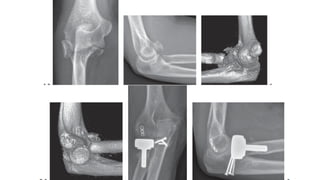

OPERATIVE MANAGEMENT

• OPEN REDUCTION AND INTERNAL FIXATION

• INDICATIONS

• Mason type 2 with mechanical block (displaced)

• Large fragment >2 mm

• Mason type 3 (> 3 fragments)

• Mechanical block to mo)on

• Presence of other complex ipsilateral elbow injuries (without metaphyseal bone loss)

• Mini fragments screw ( 2.4 or

2.7mm) .

• Headless compression screw/ Herbert

screw .

• Mini t plate (in safe zone)